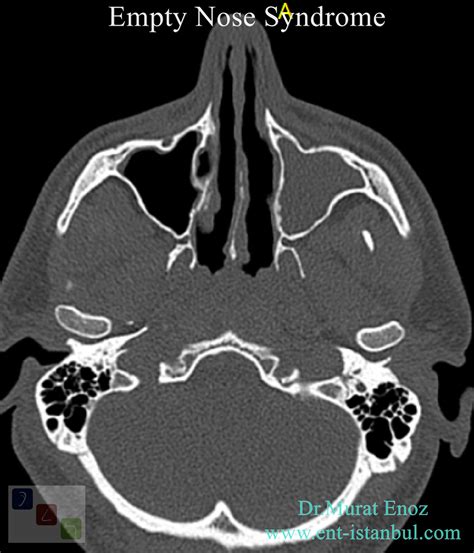

• Imaging Studies: CT scans or MRI can provide detailed images of the nasal structures and help identify any abnormalities.